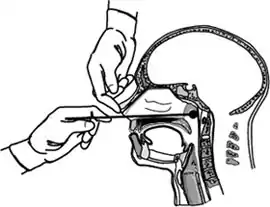

Wikimedia Commons har flere filer relaterede til COVID-19 testing – Coronaviridae- "Instruks for prøvetagning" Arkiveret 23. september 2020 hos Wayback Machine fra Rigshospitalet.dk, afsnit for luftvejssekreter